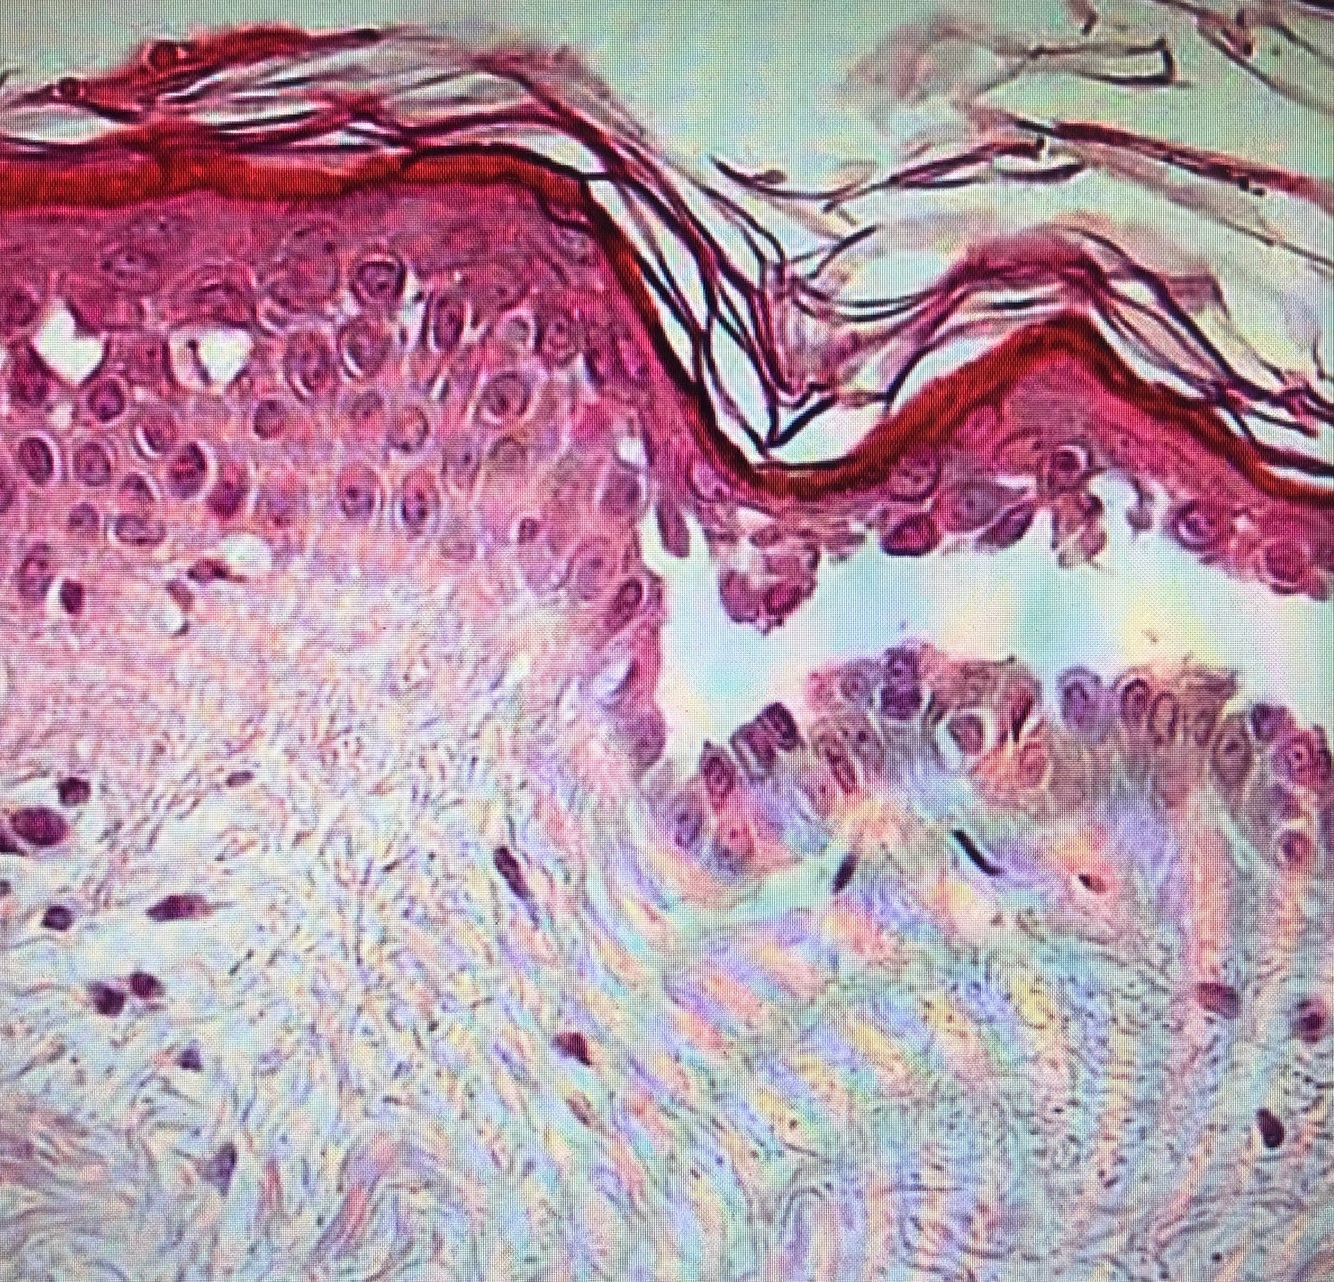

Qual diagnóstico?

PV (clivagem suprabasal, acantolise)